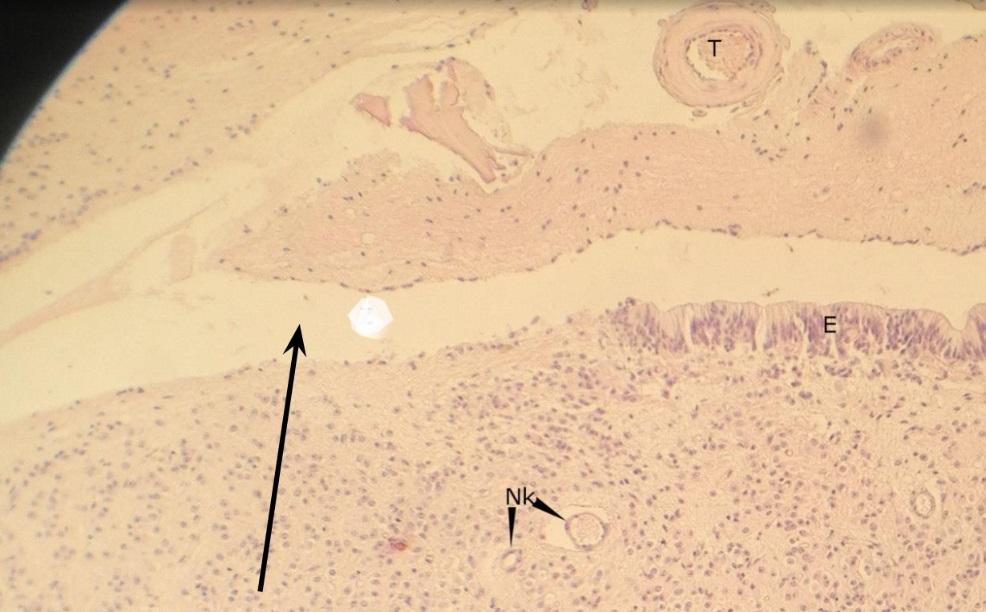

Pytanie 262

zachyłek komory trzeciej (szyszynka)

Pytanie 263

nabłonek ependymalny - ependymocyty (szyszynka)

Pytanie 264

naczynie krwionośne (szyszynka)

Pytanie 265

pinealocyty (szyszynka)

Pytanie 266

opona miękka (szyszynka)

Pytanie 267

pola glejowe - jasne ciapki z komórkami śródmiąższowymi glejowymi (szyszynka)

Pytanie 268

pinealocyty - skupiska (szyszynka)